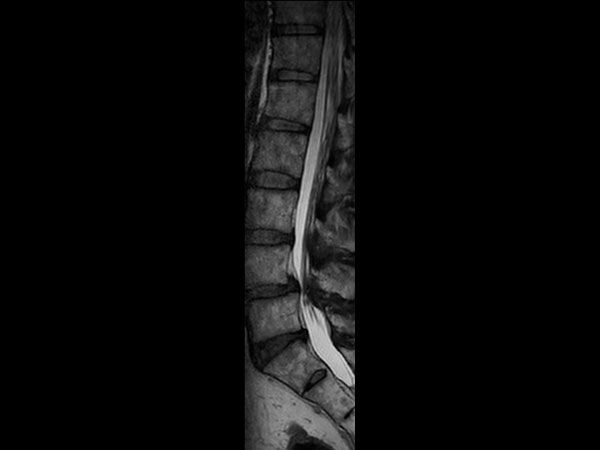

Lumbar Spine disc herniation

Patient with a lumbar spine disc herniation.